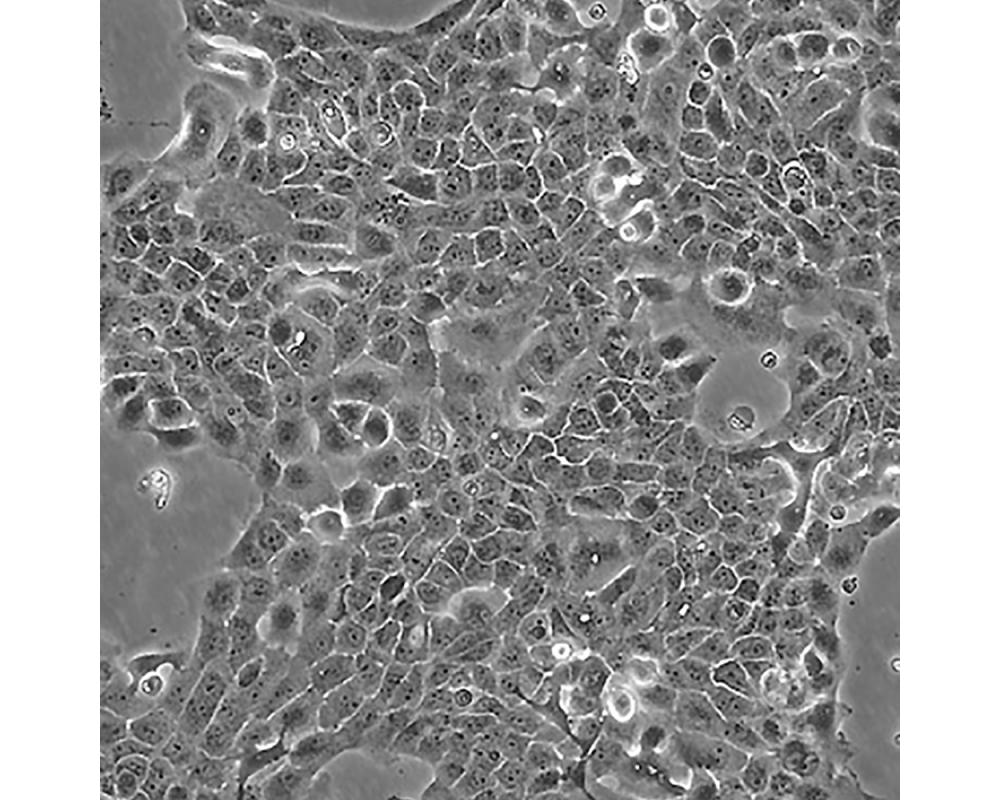

A-431(A431,A 431)

中文名稱 人皮膚鱗癌細胞

組織來源 外陰鱗狀細胞癌;女性

生長特性 adherent

培養基 DMEM+10% FBS+1% P/S

形態特征 epithelial

細胞描述 該細胞源自一位患有皮膚鱗狀細胞癌的85歲女性,是GiardDJ等人建立的一系列細胞株中的一株。該細胞在免疫抑制小鼠體內可成瘤,在瓊脂上培養可形成克隆;是一個超三倍體人細胞株。